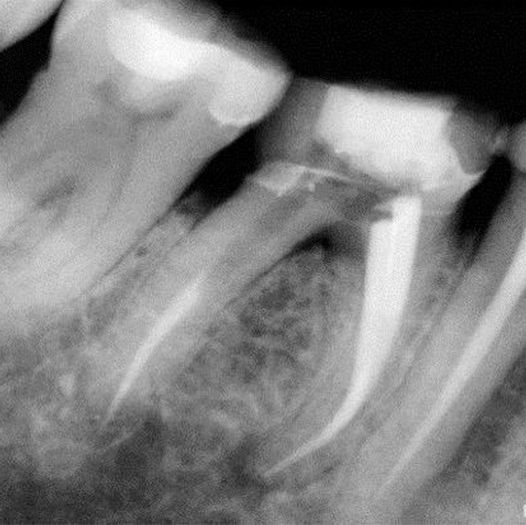

Before

Before Root Canal treatment